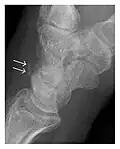

Figure 4: Dorsal triquetral fracture of the left wrist in a 30-year-old man after a trauma. (a) Anteroposterior radiograph shows a normal appearance. (b) Lateral radiograph of the same wrist demonstrates a chip fracture off the dorsal aspect of the triquetrum (arrow).[1]